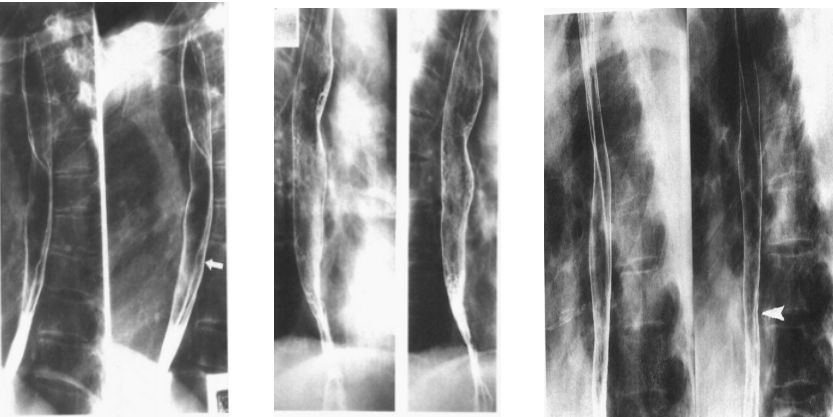

食管平滑肌瘤:指压征,环形征。

单发的食管平滑肌瘤

多发的食管平滑肌瘤